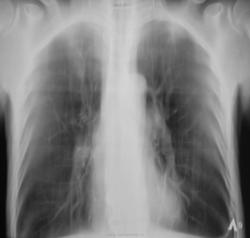

"Динамика"..., или "гнилой" случай...

Как всегда зацепили по "флюшке"..., и сами не рады, дообследовали.

Но, фтизиатр не "возбудился", решил понаблюдать, назначил контроль через 2 месяца.

И, ещё контроль через 6 месяцев.

И, еще через 6 месяцев.

"Флюшка" - от вчера.

Какие мнения будут уважаемые коллеги?

"История похождения бравого туберкулёза"